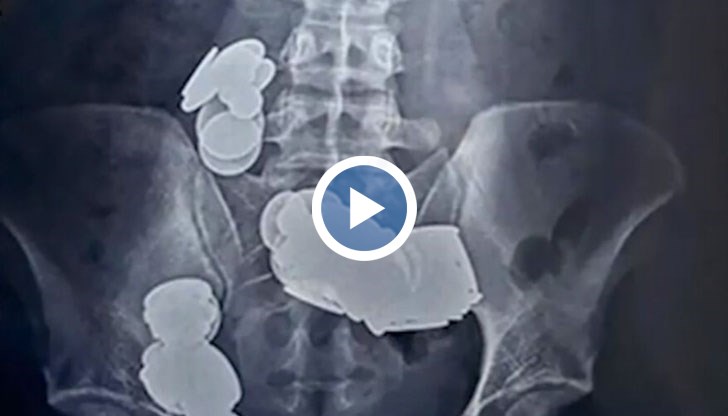

Пациентът не можел да яде нищо. Според близки на културиста той се почувствал зле, тъй като от няколко седмици гълтал монети и магнити. Лекарите му направили рентген и се уверили, че в коремната му кухина има десетки чужди тела. Мъжът претърпял спешна операция, по време на която станало ясно, че магнити и монети са попаднали в две различни извивки в тънките му черва. Магнитите се слепили и така наранили червата. В стомаха на културиста са открити и голям брой метални предмети. Лекарите са извадили общо 39 монети и 37 магнита от корема на пациента.